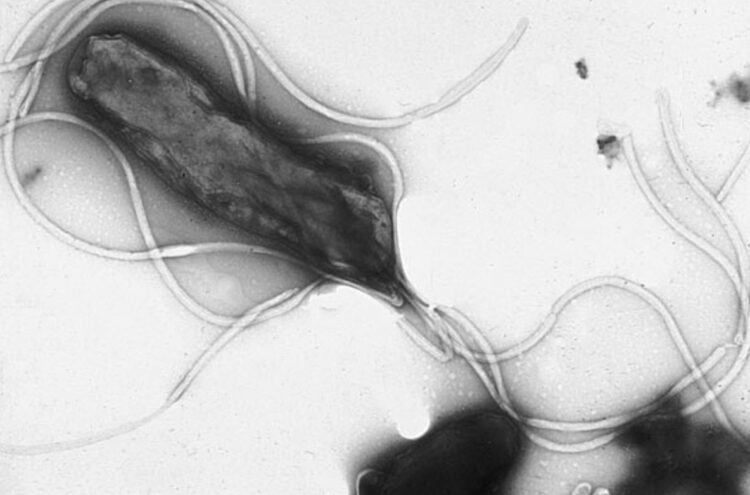

Бактерия Helicobacter pylori под микроскопом. Источник изображения: wikimedia.org